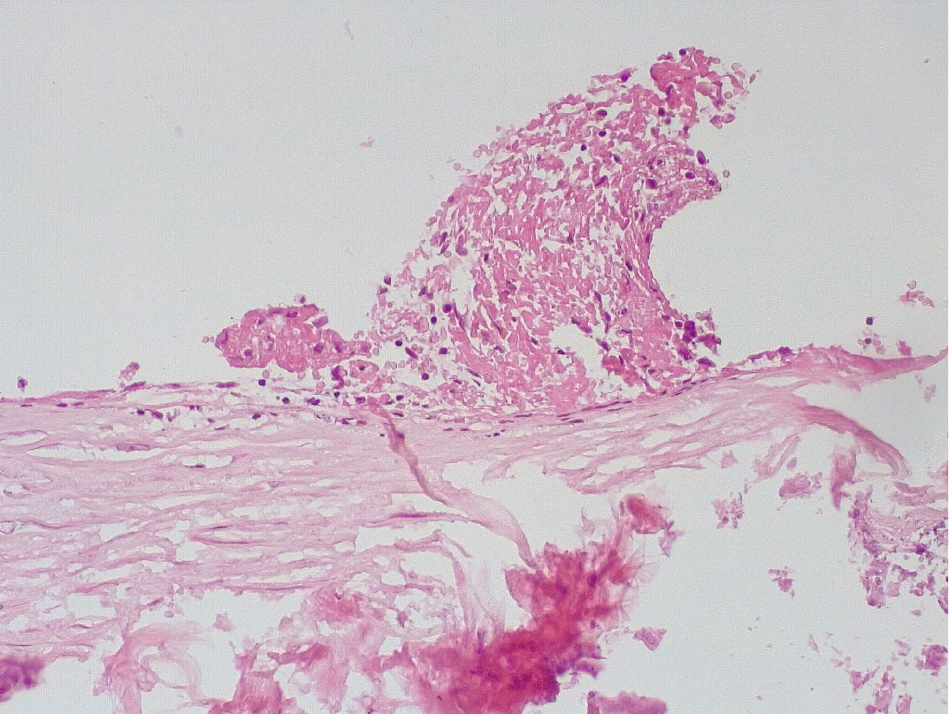

Позднее, спустя 3–7 суток после стентирования КА в просветах имелись пристеночные смешанные фибриново-лейкоцитарные тромбы, которые могли служить источником развития тромбоэмболических осложнений мелких дистальных ветвей коронарного кровотока и развитием острого инфаркта миокарда (рис. 4).

Маркер эндотелиальной дисфункции – фактор Виллебранда (ФВ) ярко экспрессировался в клетках эндотелия КА и субинтимально, что могло свидетельствовать о выраженной дисрегуляции коагуляционных свойств крови (рис. 5). В то же время экспрессия белка CD31 в указанные сроки после стентирования была слабовыраженной, что могло указывать на выраженные дистрофические изменения эндотелиальных клеток КА.

В течение 7–15 суток после стентирования КА наряду с формированием пристеночных фибриновых тромбов с признаками организации в стенках атером наблюдались репаративные процессы, связанные с неоангиогенезом в виде образования мелких тонкостенных кровеносных сосудов капиллярного типа, окруженных мелкими лимфоцитарными, гистиоцитарными клеточными инфильтратами (рис. 6, 7).